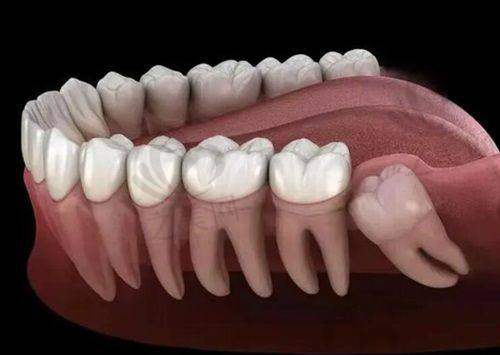

德国激光美学种植:这是门诊部的特色种牙项目之一。德国激光美学种植技术结合了激光技术和美学理念,在种植牙齿的过程中,能够更加精细地定位,减少对周围组织的损伤,同时注重牙齿的美观度和功能性。对于牙齿缺失的患者来说,是一种较为理想的种植方式。